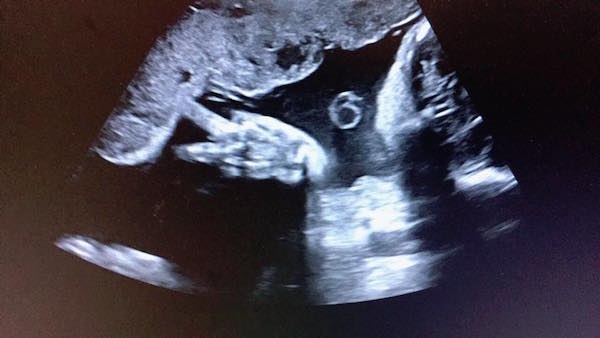

▼最近她有貼出女兒超音波照,顯示Tammy竟在裡面比出「YA」的手勢,崩潰失笑說:「媽咪每天嗑一堆藥辛苦安胎~妳在裡面倒是挺開薰的嘛!還有空比YA勒…算妳狠!」也附註Tammy已經有1300多公克,「給我乖乖待著,時間到了才准出來嘿!」

▼從照片中也可以看到,Tammy照片漸漸清晰,長得與哥哥Willson十分神似,讓嚴立婷也很期待妹妹能出生,「覺得以後兄妹會長很像,你們說如果Tammy像Willson是不是挺不賴的?」Tammy小腿也相當修長,底下網友大贊遺傳父母優秀基因,以後一定是「小美女」。